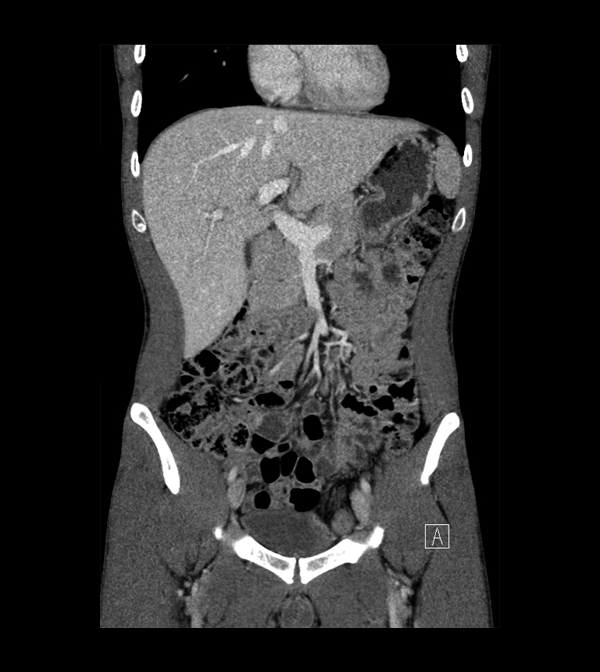

Body

Covers abdominal CT anatomy.